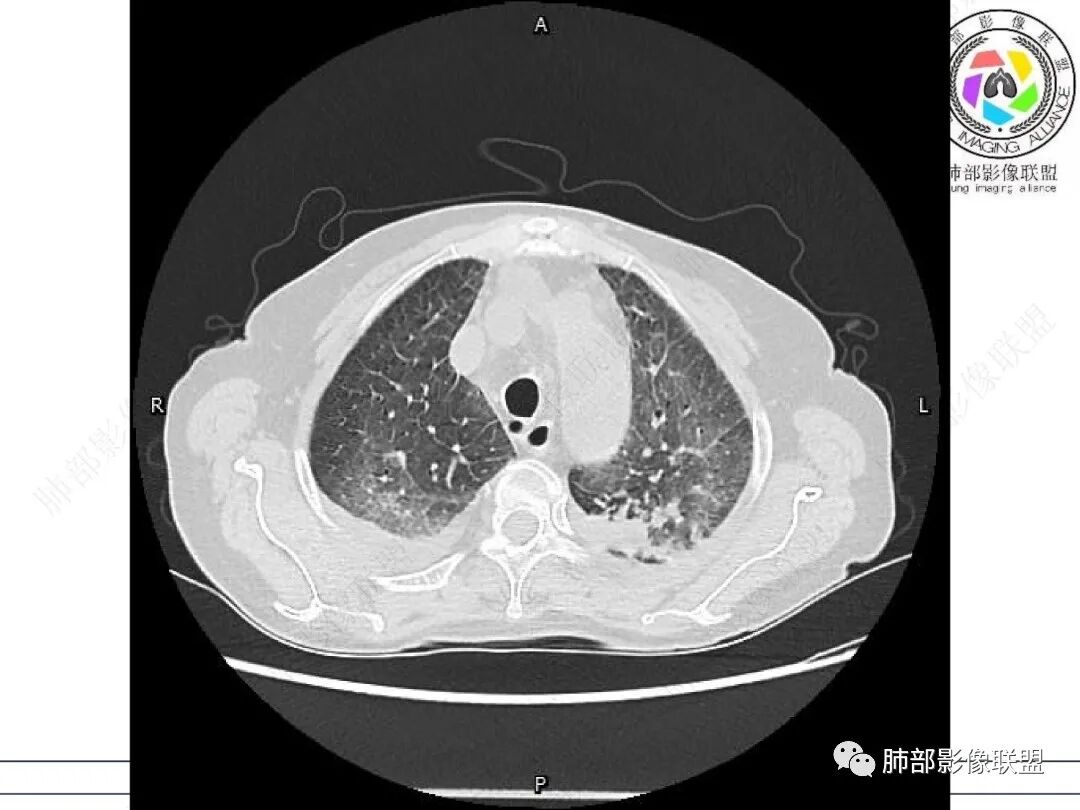

发热,有类风湿性关节炎、糖尿病基础病,长期口服激素及免疫抑制剂,双肺多发磨玻璃影及小叶间隔增厚,蜂窝影,支气管扩张考虑非特异性间质性肺炎存在,左肺上叶不规则结节影,周围长毛刺局部肺气肿,考虑慢性炎症,结合pct及crp升高考虑细菌感染,另真菌g升高考虑结合宿主因素,真菌感染需要积极排除。

老年,外阴溃疡加发热,感染指标明显有异常,血气分析,过度呼吸及低氧血症,宿主因素,糖尿病和激素,基础疾病RA。影像,双下肺体积有缩小,有蜂窝?双肺磨玻璃,多发结节,双侧胸水。树芽不明确。是否有旧片,这个患者有UIP背景,是否感染或者UIP急性加重,或者基础上合并肺栓塞及肺水肿?长期激素,没有提供CD4细胞亚群,存在2种情况,1,风湿病没有压制住,肺考虑CTD相关性间质改变,压制过猛,结合感染指标,奴卡是有可能的。激素加糖尿病,结核也带排,激素加磨玻璃加G实验阳性,PCP也带排,临床信息太少,进一步排查

女,71,外阴疼痛2周,发热1周。类风关、高血压、高血糖、卵巢囊肿、肠粘连、胆囊结石等病史及相关药物治疗史。胸部CT:两肺弥漫磨玻璃,血管束增粗,两下肺后肋膈角多发蜂窝,对称分布,双侧胸腔少量积液,纵隔窗心脏大血管影明显增宽。考虑混合性病变,CTD-ILD,并肺水肿?并PJP?。

双肺下叶多发蜂窝影,双肺小叶间隔增厚,双肺磨玻璃影,双侧胸腔积液,有类风湿性关节炎,考虑结缔组织相关性间质性肺病,合并感染

①影像表现复杂:较弥漫间质性改变,对称磨玻璃密度为主,小叶间隔增厚,有一定重力分布趋势,未见明显纤维化,气囊及蜂窝位于肺边缘,未见典型“月弓征”。心脏影增大,双侧胸腔积液。

这即可见于间质性肺病,也可见于真菌感染(如PJP)、病毒感染,类风湿,以及肺水肿等等。

一般而言,如存在磨玻璃密度影浑浊,有重力分布趋势,肺表面蜂窝影,胸腔积液等等,并不常见于单纯PJP,除非其他因素叠加。

患者存在肺水肿应当是合理的解释。其他旁证还有,心脏影增大,肾小球滤过率降低,双侧胸腔积液等等……